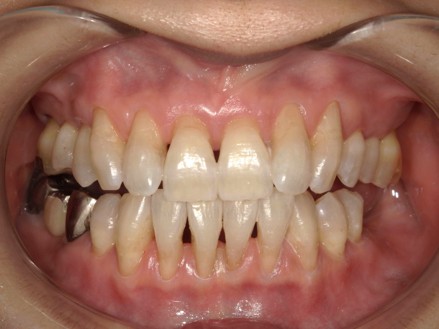

治療後

| 術後の経過・現在の様子 | ホワイトニング後は、黄色味が抜けて全体的に統一感のある状態に仕上がったと思います。 ステイン除去後、口腔内への意識変化からホワイトニングまで行いました。 長年気になってはいたけど、そのままにしていたステインと歯の色だったそうです。ホワイトニング終了後の仕上がりには大変満足されていました。 今後は出来るだけ今の状態をキープしていきたいとの事で、着色予防のために始めに行っていたパウダーを使ったメンテナンスを継続していきます。 今後も患者さんの理想の口腔内を保てるようにサポートしていきます。 |